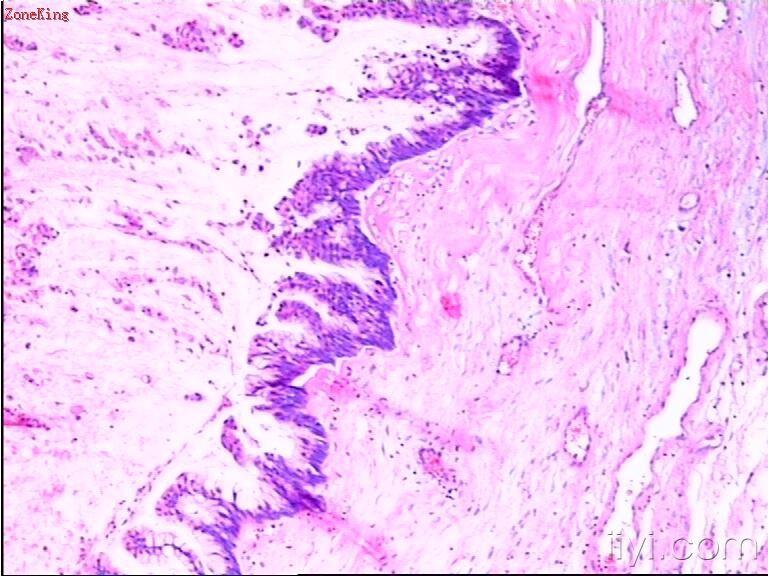

睾丸肿物,30岁,肿物位于睾丸白膜内,紧靠白膜,切面呈胶冻状。

部分区被覆上皮为粘液性上皮,考虑为粘液性囊腺癌;

30岁男子,睾丸肿块,有以下考虑:1. NSGCT2. 睾丸类癌。可以作为NSGCT的一个成分,也可以是来源于自身内分泌细胞的一个原发肿瘤或者是来自胃肠道肿瘤的一个转移瘤。 建议进一步做相关免疫组化(PLAP、AFP、HPL、NSE、PSA、β-HCG、CD30、EMA等待)或全面检查确诊。